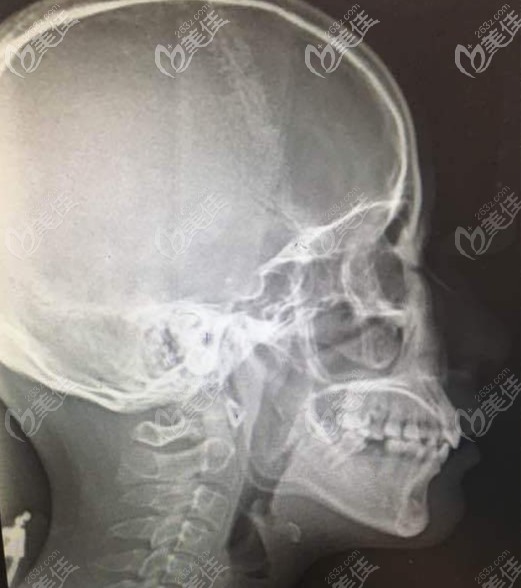

這是我的2級骨性齙牙的頭顱片▲

如果確定是骨性前突就建議盡早做治療,有些復雜的牙齒情況靠單純的正畸整牙已經很難達到好的效果了,必須要配合正頜手術,才能達到良好的效果。

所有的牙齒錯頜問題在矯正前都要經過取模、X線頭影測量、醫(yī)生的準確分析后在進行矯正。

相對于牙性前突,骨性的齙牙要更耗時間更麻煩,所以費用也貴,一般矯正的費用在3萬元起,如果是正畸正頜聯合手術,費用大概在8萬元起。